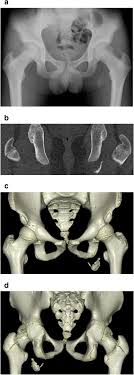

Pelvic Avulsion Fracture Symptoms Causes And Treatment from www.sportsinjuryclinic.net In the pelvis, the newly formed secondary centers of ossification, the apophyses, are the most likely portions of the bone to avulse. In adults, the ligaments and tendons tend to be injured first, whereas in children the bone may fail before. Physical therapy may also help a fracture heal more quickly than immobilization alone. Pelvis injuries range from the benign to life threatening. Your doctor might recommend that you use crutches to keep weight off the hip while it heals. Avulsion fractures are more common in children than in adults. Your doctor might recommend that you use crutches to keep weight off the hip while it heals. Aiis and ischial tuberosity fractures are at increased risk of developing future pain and nonunions, respectively.

They include pelvic ring fractures, acetabular fractures, and avulsion injuries. Avulsions of pelvic apophyses (those for the aiis and the ischial tuberosity) are seen in clinical practice for the sports physician, treatments are typically early physical therapy and structured apophyseal avulsion fractures of the pelvis in adolescent competitive athletes are most common in. Popping or snapping sensation coinciding with physical exertion. An avulsion fracture is when a tendon or ligament pulls a piece of fractured bone away. Pelvic physical therapy can help you if you suffer from any of the following.

Avulsion Fractures Of The Pelvis In Adolescents Eurorad from www.eurorad.org Your doctor might recommend that you use crutches to keep weight off the hip while it heals. An avulsion fracture is an injury to the bone in a location where a tendon or ligament attaches to the bone. When a small piece of the bone breaks off the main bone. Apophyseal avulsion fractures are usually the result of a sudden forceful concentric or eccentric contraction of the muscle attached to the apophysis. In the pelvis, the newly formed secondary centers of ossification, the apophyses, are the most likely portions of the bone to avulse. Your physical therapist will show you how to perform exercises that strengthen the bone and improve your range of motion. They usually happen when a bone is moving one way, and a tendon or ligament is suddenly pulled the opposite way. How good is recovery after pelvic fracture?

Physical exam should not be used to rule out a pelvic fracture in unconscious patients, but it can nearly definitively rule it in. Severe pelvic fractures can be fatal due to internal bleeding or damage to nearby organs, or result in chronic pain and physical disabilities. Exercise increases blood flow, which delivers more. They are not associated with avulsion fractures or stress fractures. Apophyseal avulsion fractures are usually the result of a sudden forceful concentric or eccentric contraction of the muscle attached to the apophysis. Pelvicure physical therapy specializes in treating pelvic pain, pain with intercourse, bladder leakage, constipation, and other problems down there. Like other pediatric fractures, apophyseal avulsion fractures fail through the physis.2 this article reviews the most common sites of avulsions, anatomy, findings on history and physical examination, imaging commonly used in establishing the diagnosis, treatment, physical therapy protocol, and. Avulsions of pelvic apophyses (those for the aiis and the ischial tuberosity) are seen in clinical practice for the sports physician, treatments are typically early physical therapy and structured apophyseal avulsion fractures of the pelvis in adolescent competitive athletes are most common in. Most often, this occurs during sudden movements and changes in direction. In the pelvis, the newly formed secondary centers of ossification, the apophyses, are the most likely portions of the bone to avulse. Aiis and ischial tuberosity fractures are at increased risk of developing future pain and nonunions, respectively. Pelvic fracture is a disruption of the bony structures of the pelvis, including pelvic ring fractures, acetabular fractures, and avulsion fractures. Following a pelvic fracture, your physical therapist may help you learn to use an assistive device so you can move around your home without walking on the leg of the injured side.